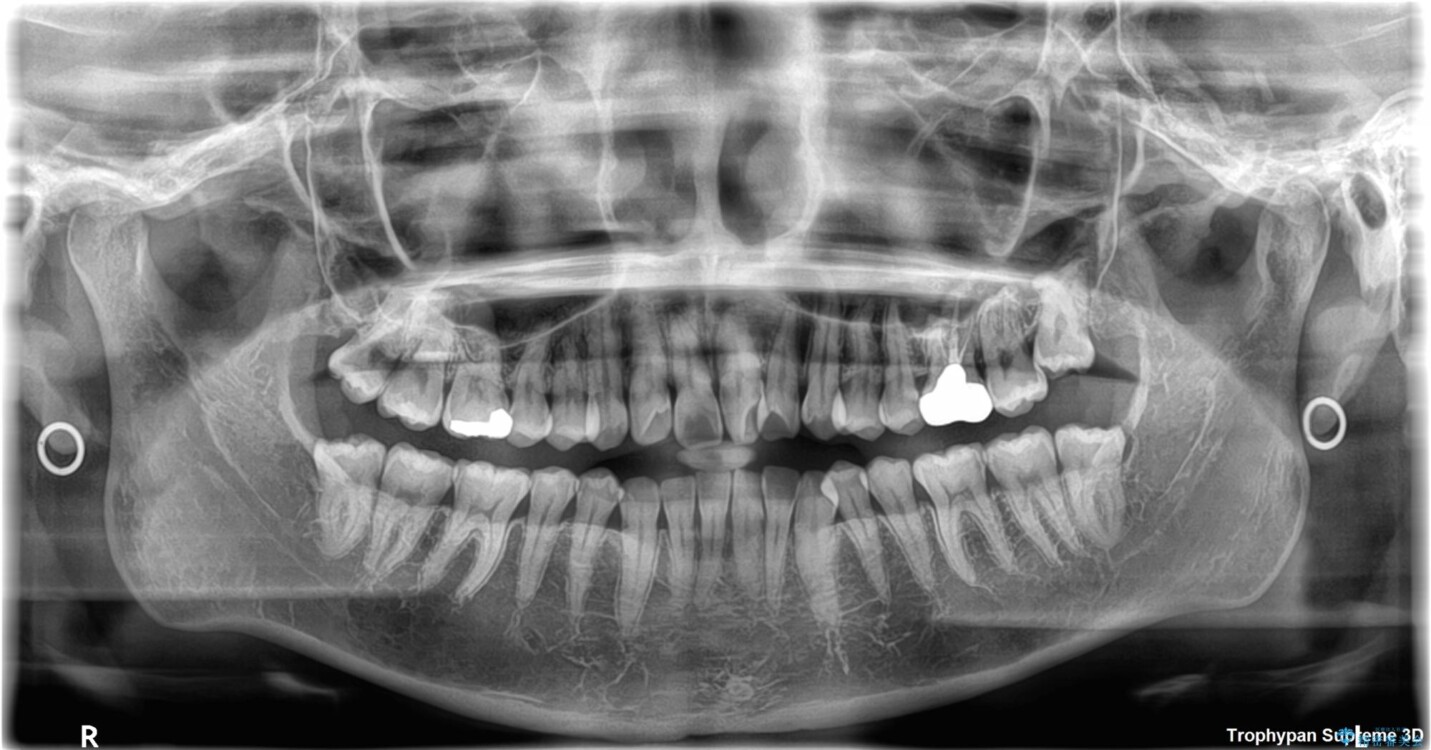

◆ 診断と治療計画

診察の結果、上下の前歯部に**叢生(そうせい/歯のガタガタ・重なり)**が認められました。

特に上の前歯にはねじれや重なりがあり、審美的にも清掃性にも影響している状態でした。

治療方法としては、装置の目立ちにくさと費用面のバランスを考慮して、プラスチック製のクリアブラケットとメタルワイヤーを組み合わせた矯正装置を使用することにしました。

また、上顎前歯の重なっていた部分にはむし歯が見つかり、治療中に適切な処置を行っています。